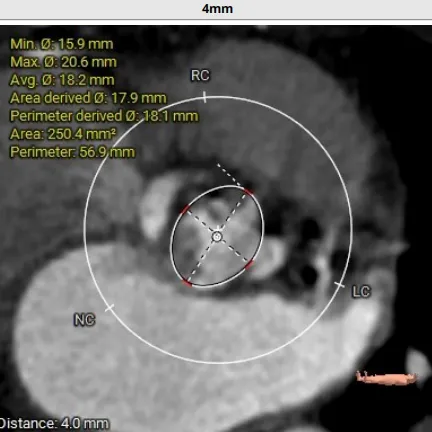

术前CT评估:TYPE 0型二叶瓣,瓣叶肥厚,前后交界粘连,瓣叶无明显钙化,双冠异窦,左冠开口高度约16.6mm,右冠开口高度约16.7mm。法式窦结构小,STJ高度约21.6mm,直径约24.4mm,升主动脉未见明显增宽,心脏角度约42°,左室大小尚可,心尖部可见局部心肌薄弱。

入路情况:主动脉弓部走行欠佳,主动脉弓部各主要分支开口处未见明显狭窄征象、未见发育变异,胸主动脉、腹主动脉走行较平直,管腔未见明显狹窄,双侧髂动脉-股动脉走形较平直,管腔未见明显狭窄,综合考虑,推荐右侧股动脉做为主入路,右侧股动脉穿刺水平管腔直径约为5.8mm,右侧股动脉分叉约在股骨头下1/3水平。

手术策略:多学科精心谋划,制定个性化策略